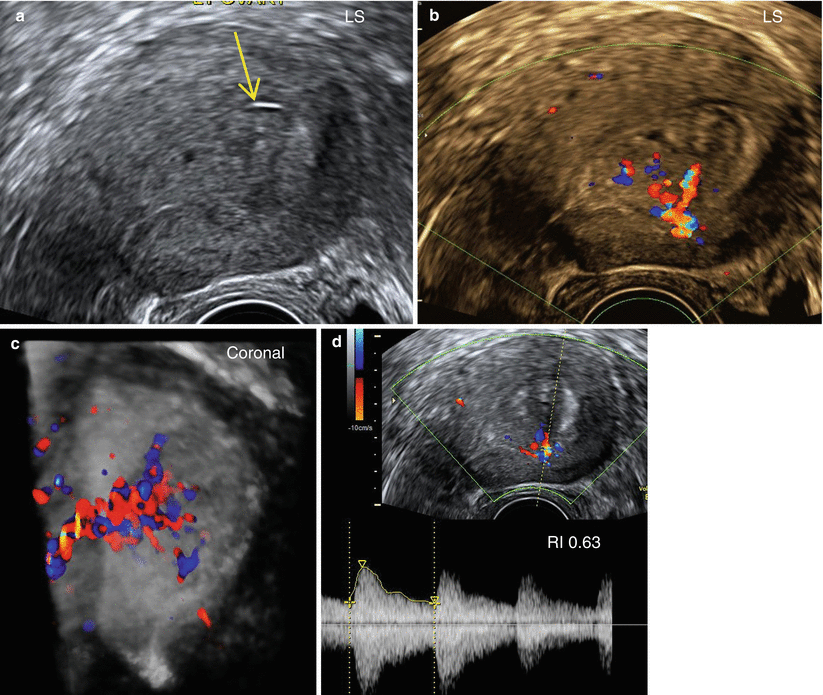

From www.researchgate.net

Ultrasound images of a female patient, aged 55years with thickened Thickened Endometrium Results Endometrial hyperplasia involves the thickening of the endometrium, which lines your uterus. Tamoxifen is known to raise the risk of endometrial hyperplasia and cancer. The only way to tell for certain that cancer is present is to. Endometrial cancer is the major concern with an abnormally thickened endometrium. Endometrial hyperplasia is a condition in which the lining of your womb. Thickened Endometrium Results.